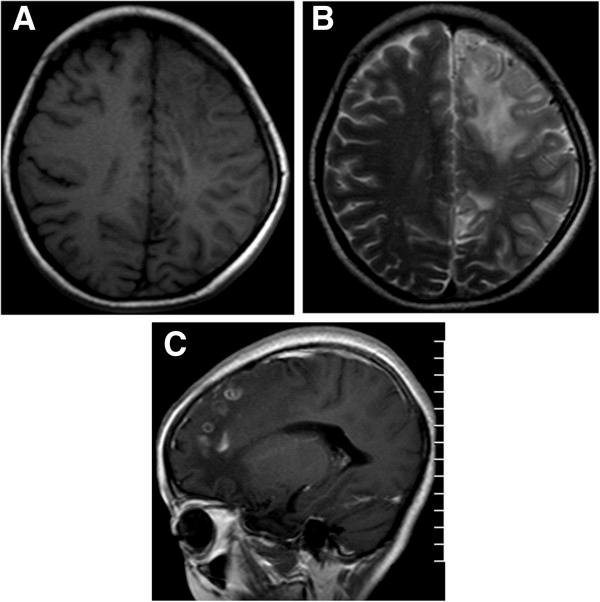

Twenty-seven lesions were found in the eighteen children. Twelve lesions in twelve patients were solitary while the lesions in the rest six patients were multiple and asymmetrical. The positions of the lesions were: seven in frontal, eleven in parietal, four in temporal and two in occipital lobes, one in basal ganglia, one in cerebella hemisphere and one in pons. The lesions were presented as slight hypointensity on T1-weighted images but moderate hyperintensity on T2-weighted images with perilesional brain parenchyma edema. Enhanced MR scans by using Gadopentetic Acid Dimeglumine Salt were performed in the patients, and the images demonstrated abnormal enhancements with the patterns of a peripheral ring, or a tortuous beaded, or a serpiginous tubular shape. Follow-up MR scans were preformed for eight patients, and three out of the eight cases exposed migrations and changes in shapes of the lesion areas.

18 例患儿共发现 27 个病灶。12 例患儿的 12 个病灶为单发,其余 6 例患儿的病灶为多发且不对称,病变部位:额叶 7 个,顶叶 11 个,颞叶 4 个,枕叶 2 个,基底节区 1 个,小脑半球 1 个,脑桥 1 个。病灶 T1WI 呈稍低信号,T2WI 呈等或稍高信号,周围脑实质水肿。增强 MRI 扫描均采用钆喷酸葡胺,病灶呈异常强化,强化形式有:周边环状、迂曲串珠状或蜿蜒管状。8 例患儿进行了随访 MRI 扫描,其中 3 例病灶部位出现迁移和形态改变。